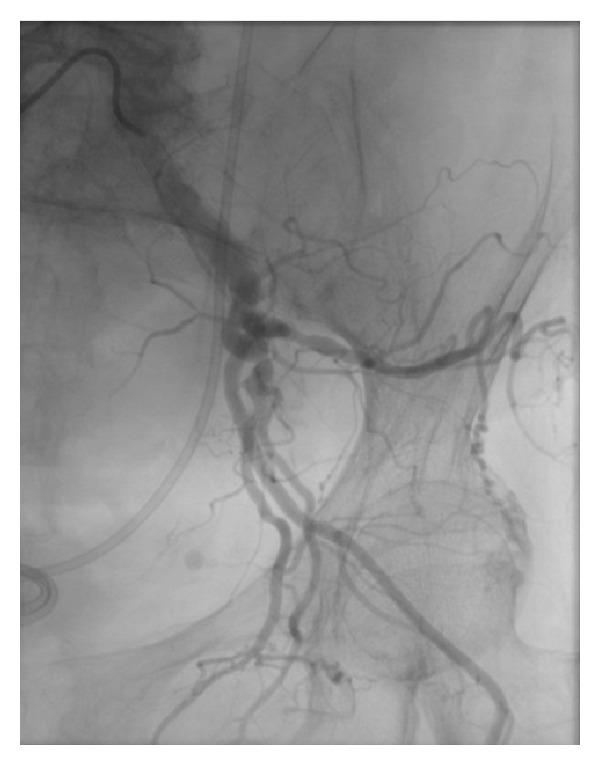

Arteriographic evaluation of vascular changes of the extremities in patients with systemic sclerosis.

Br J Dermatol. 2006 Dec;155(6):1159-64. doi: 10.1111/j.1365-2133.2006.07475.x.